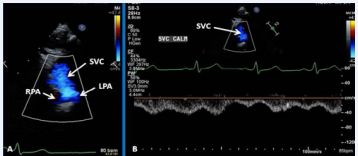

Figure 25 Selected video frames from suprasternal notch view demonstrating bidirectional Glenn shunt; the superior vena cava (SVC) is shown emptying into the right (RPA) and left (LPA) pulmonary arteries by color flow imaging (A). Low Doppler flow velocity across the shunt (B) indicates unobstructed Glenn [69].

Figure 25 :Selected video frames from suprasternal notch view demonstrating bidirectional Glenn shunt; the superior vena cava (SVC) is shown emptying into the right (RPA) and left (LPA) pulmonary arteries by color flow imaging (A). Low Doppler flow velocity across the shunt (B) indicates unobstructed Glenn [69].

Figure 26 Selected video frames from suprasternal notch view demonstrating bidirectional Glenn shunt; the superior vena cava (SVC) is shown emptying into the right (RPA) and left (LPA) pulmonary arteries by two dimensional (A) and color flow imaging (B) [69].

Figure 26: Selected video frames from suprasternal notch view demonstrating bidirectional Glenn shunt; the superior vena cava (SVC) is shown emptying into the right (RPA) and left (LPA) pulmonary arteries by two dimensional (A) and color flow imaging (B) [69].

Echocardiographic and angiographic examples of the bidirectional Glenn procedure are shown in Figures 25-28.